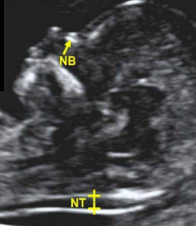

when is NT measured

11-13.5 weeks

normal measurement of NT

2.5-3mm

equal sign

top- skin

when do the nasal bones first appear

11-13 weeks 6 days

CRL of 42mm